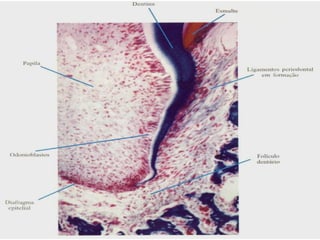

PeriodontogênesePeriodontogênese

• A formação do periodonto de inserção (cemento,A formação do periodonto de inserção (cemento,

ligamento periodontal e osso alveolar) se dáligamento periodontal e osso alveolar) se dá

simultaneamente a formação da raiz;simultaneamente a formação da raiz;

• A fragmentação da bainha radicular coloca oA fragmentação da bainha radicular coloca o

folículo dental em contato com a dentinafolículo dental em contato com a dentina

radicular, ocorrendo indução de diferenciação deradicular, ocorrendo indução de diferenciação de

células do folículo dental em cementoblastos ecélulas do folículo dental em cementoblastos e

secreção de matriz orgânica do cemento.secreção de matriz orgânica do cemento.

• Células centrais do folículo dental se diferenciamCélulas centrais do folículo dental se diferenciam

em fibroblastos e formam o ligamentoem fibroblastos e formam o ligamento

periodontal;periodontal;

• Células da periferia se diferenciam emCélulas da periferia se diferenciam em

osteoblastos e formam o osso alveolarosteoblastos e formam o osso alveolar

propriamente dito;propriamente dito;

• As fibras do ligamento são formadas ao mesmoAs fibras do ligamento são formadas ao mesmo

tempo que a matriz do cemento e osso,tempo que a matriz do cemento e osso,

possibilitando sua inserção nestes tecidos, sendopossibilitando sua inserção nestes tecidos, sendo

chamadas FIBRAS DE SHARPEY.chamadas FIBRAS DE SHARPEY.